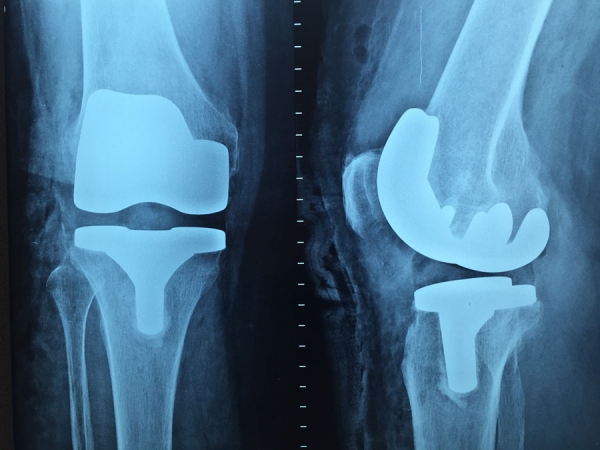

Ortopédia